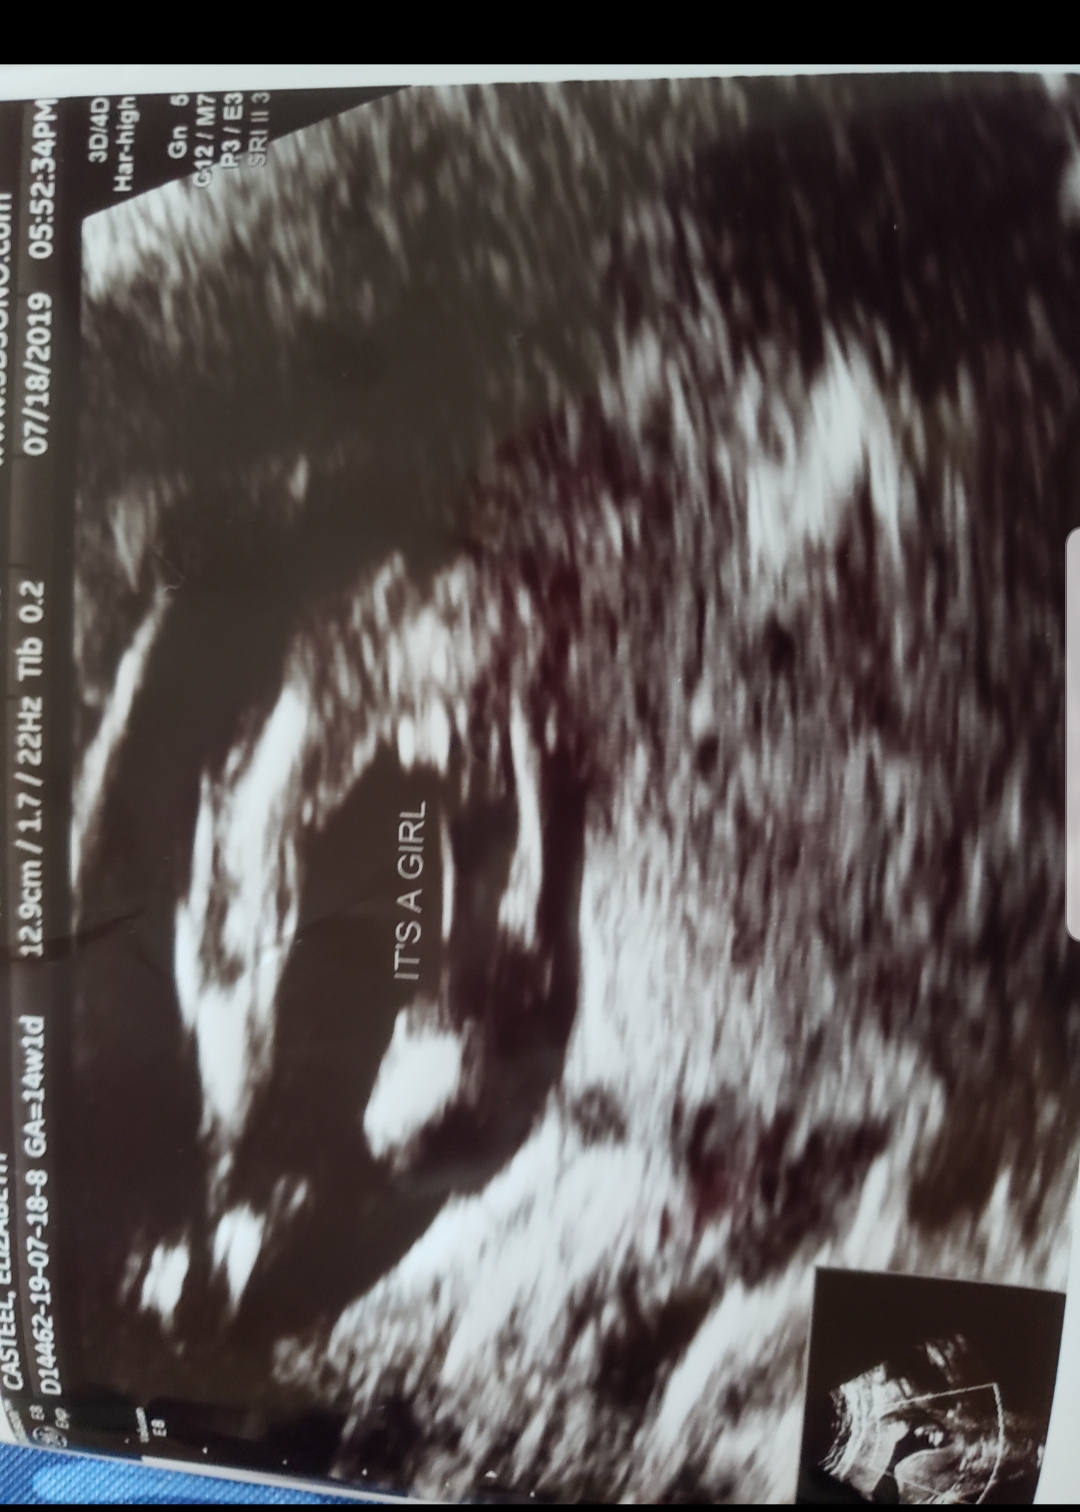

Attachment 41847

I went in for a 16+1 ultrasound and it looks like it's definitely a girl!! (The sonographer triple checked it!)